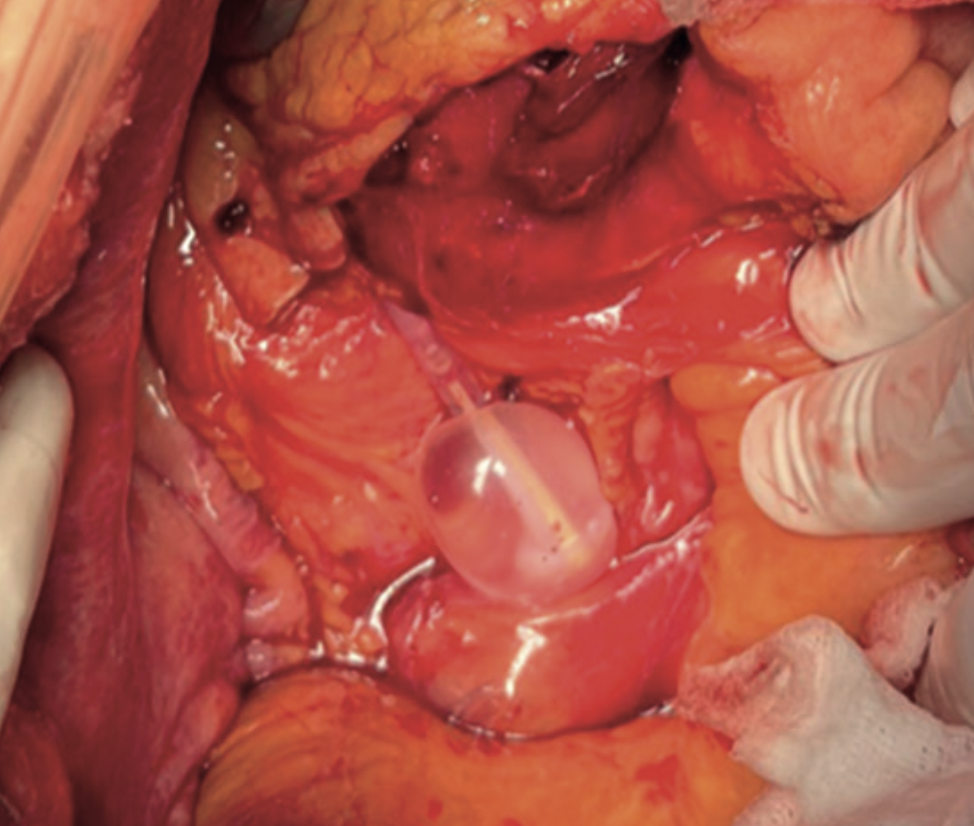

Luz Alejandra Lorca Parraguez, Cinara Sacomori, Marta Pizarro, Ivana Leao Ribeiro, Rodrigo Vidal, Gonzalo Rebolledo Rebolledo

|

|

|